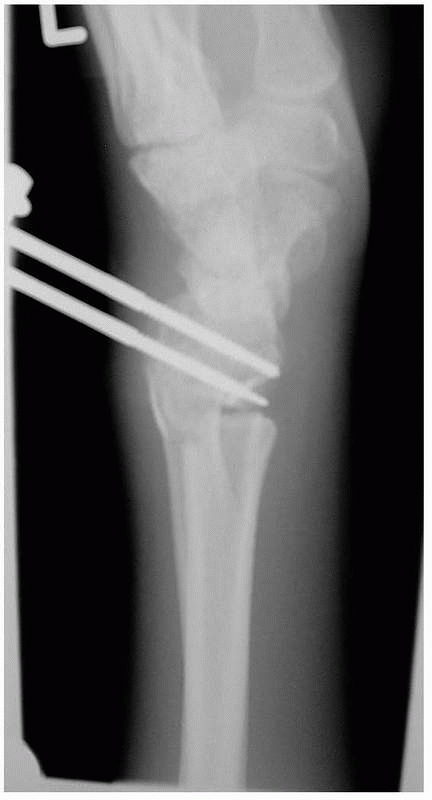

![]() |

FIGURE 30-22 A.

A fluoroscopic view of the distal pins for a nonbridging external fixator. The fracture is unreduced and the pins have been inserted parallel to the radiocarpal joint, between the fracture and the joint and engaging the volar cortex. B. The fracture has been reduced into palmar tilt using the pins as a “joystick.” Note the defect in the dorsal cortex from dorsal comminution. |